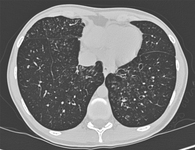

Sinais do anel de sinete em uma mulher de 20 anos de idade com bronquiectasia

De Pamela J. McShane, MD; uso autorizado